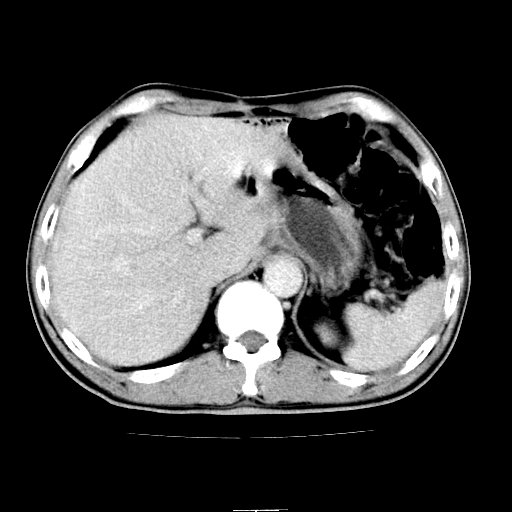

患者男,64岁,胃癌术后三个月,无明显不适。请讨论一下胰头前方小圆形低密度影为淋巴结还是肠管?

增强第6幅图上有气液平相通,是肠管,右肾低密度灶形态不规则似有壁结节,不除外转移.

应该考虑是肠管,理由1、平扫和增强对比,形态和内部的密度有明显改变。2、增强图片可见明显气液平面。

另外,胰腺体部密度在平扫和增强时均不太均匀,似有数个小的囊状低密度区存在。不知道增强时其他期如何?应该高度警惕为转移性病变。

胰头右侧低密度影卡考虑为肠管;胰头前部低密度影,增强环形强化,结合临床首先考虑转移灶,其次考虑淋巴结结核(中心干酪性坏死)。